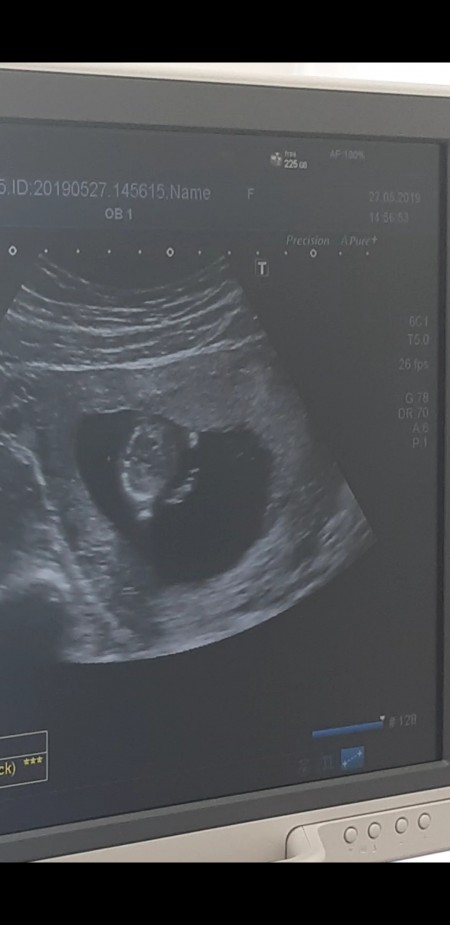

Çıldırıcam sanki yüzü yaa sevindim birden :) sizce ney bu

image

Gebelik haftası 13+4

Kafasi yada karni olabilir cnm :) cihaz iyiyse elbette yuzu gorunur :) benim gorunmustu özelde.

Canm yuz gbi ama yuzu deil bence ya

kafa ölçümüne benziyor bence